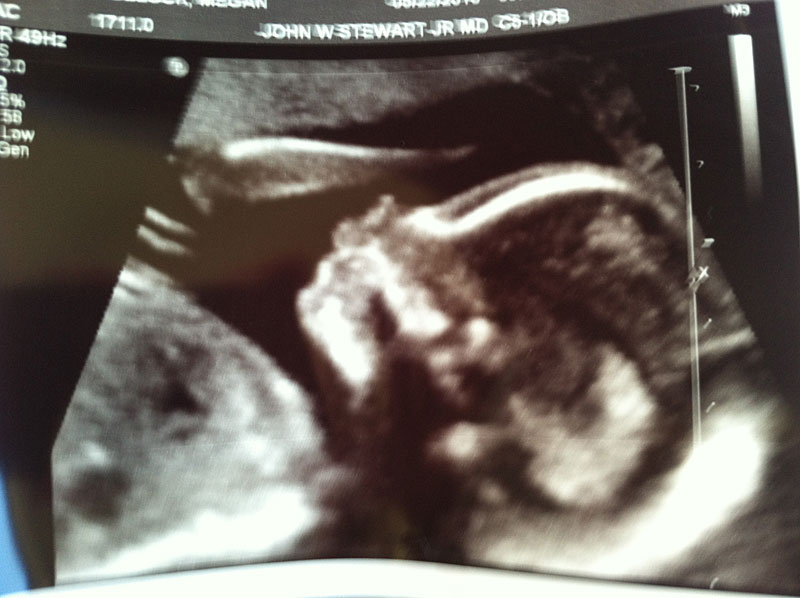

Before our first ultrasound, the staff at Dr. Stewart’s office said that my hormone levels had dropped and they would squeeze us in to take a look. What a relief to see our little P2 wiggle as Dr. Stewart’s finger followed the screen.

As much as I wanted to see the spine it was clearly too early. Dr. Stewart said we’d follow P2 closely until he felt we were safe then follow as a “normal” pregnancy.

The ultrasound was a chance for us to live our dreams and face our fear. As the ultrasound tech and Dr. Stewart followed the spine and checked for other signs of birth defects, we were given the news that P2 currently looked healthy. What a relief.